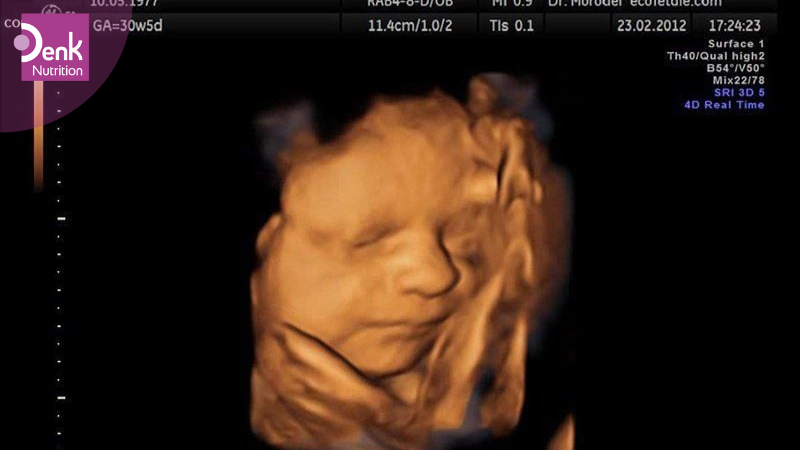

Tuần 20 – 22: Chỉ định siêu âm 4D kết hợp với các xét nghiệm cần thiết nhằm đánh giá hình thái thai nhi một cách toàn diện. Đây là giai đoạn giúp phát hiện sớm các dị tật như sứt môi, hở hàm ếch, hoặc những bất thường về cơ quan nội tạng. Bên cạnh đó, bác sĩ cũng sẽ đo chiều dài kênh cổ tử cung để tầm soát nguy cơ sinh non. Nếu phát hiện dấu hiệu bất thường, mẹ có thể được tư vấn thực hiện chọc ối để kiểm tra chính xác hơn về tình trạng sức khỏe của thai nhi. Ngoài ra, ở mốc khám này, mẹ bầu sẽ được tiêm mũi uốn ván đầu tiên để phòng ngừa nguy cơ nhiễm trùng cho cả mẹ và bé trong quá trình sinh nở.